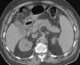

Biliary colic, also known as symptomatic cholelithiasis, a gallbladder attack or gallstone attack, is when a colic (sudden pain) occurs due to a gallstone temporarily blocking the cystic duct. Typically, the pain is in the right upper part of the abdomen. [Source: Wikipedia ]